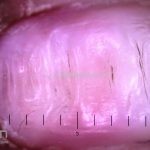

Unhas – linhas de Beau

Descrição:

São sulcos transversais na superfície da lâmina ungueal.

Causas:

Traumas, paroníquias, medicamentos, doenças cardiovasculares, infecções, anemias, onicotilomania, entre outras doenças que possam alterar temporariamente o tempo de produção ungueal.